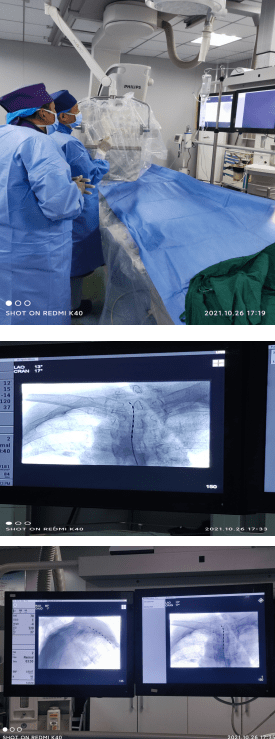

本报讯(记者王明杰 通讯员唐楠 岳永)近日,息县人民医院疼痛科主任包中喜带领岳永主治医师、陈培住院医师在河南省人民医院专家团队协助下,成功开展首例脊髓电刺激植入术治疗带状疱疹性神经痛,镇痛效果好,填补了信阳地区疼痛科脊髓电刺激技术的空白。

患者女性,75岁,左胸腹部带状疱疹后神经疼痛一月余,1月前劳累后出现左胸背腹部带状疱疹,局部阵发性针刺样疼痛,烧灼感,夜间加重,后疼痛逐渐加重,严重影响日常生活。口服普瑞巴林150mg bid,疼痛无明显缓解,患者及家人多方打听来到该院疼痛科;疼痛科包中喜主任带领团队制定了周密的治疗方案,在介入手术室密切配合及河南省人民医院疼痛科专家团队协助下成功完成了该院首例脊髓电刺激植入术。术后,患者疼痛明显减轻,VAS评分降至3分。

据该院相关专家介绍,脊髓电刺激疗法scs是一种以微量电刺激脊神经,改善慢性疼痛的治疗方法。

治疗原理: 通过植入脊髓硬膜外间隙的电极传递的电刺激,阻断疼痛信号通过脊髓向大脑传递,使疼痛信号无法到达大脑皮层,从而达到控制疼痛的目的。

脊髓电刺激(spinal cord stimulation,SCS)治疗是目前国际上公认的治疗慢性顽固性疼痛的先进疗法,它的出现使无数慢性顽固性疼痛患者摆脱了疼痛的困扰,重新扬起了生活的风帆。